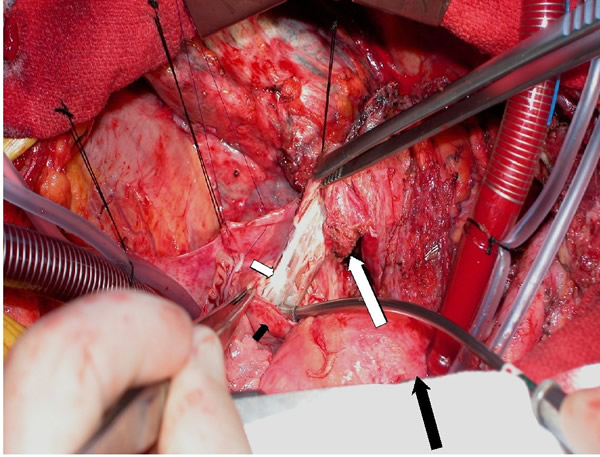

The patient was taken to the operating room and sternotomy performed after division of several large collateral chest wall veins. The pericardium was opened and resection of all thymic tissue was undertaken starting at the diaphragm (Figure 3). The SVC was transected at the confluence of the right subclavian and jugular veins and found to be filled with fibrotic tissue (Figure 4A). Frozen section examination of the luminal contents identified benign fibrotic tissue. The SVC was mobilized to the level of the right atrium en-bloc with the tumor, the azygos vein was divided, and a wedge resection of the medial aspect of the right upper lobe was performed. At this point, the tumor had been completely mobilized except for an intravascular extension through the SVC into the right atrium (Figure 4B).

The patient was placed on cardiopulmonary bypass via the aorta and inferior vena cava. The SVC was resected with the atrium and the tumor removed en-bloc (Figures 5-7). The atrium was closed and the patient weaned off cardiopulmonary bypass. The patient was extubated on postoperative day 2 and discharged home on postoperative day 7. Final pathology revealed a malignant thymoma with vascular and lung invasion.